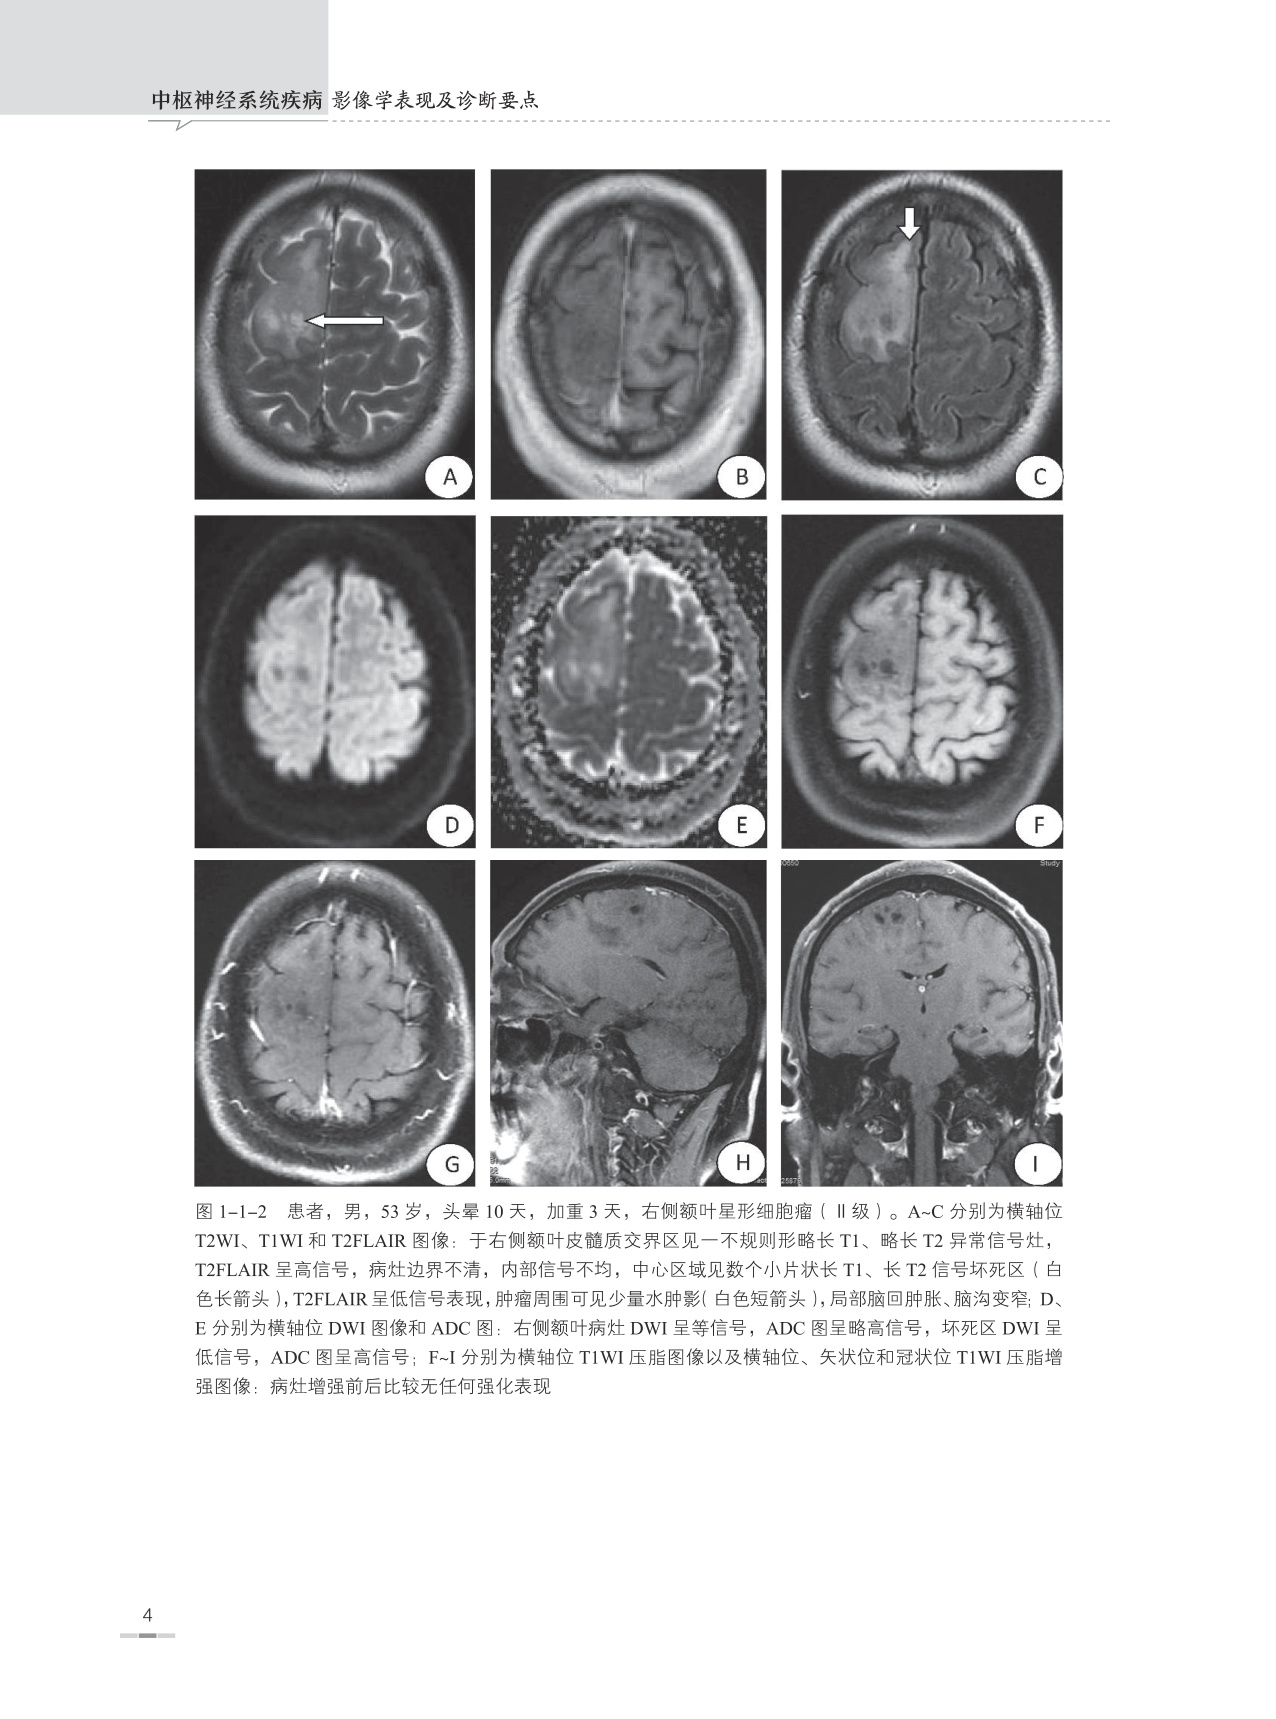

本书是根据作者本人多年临床工作经验并参考大量中外文献资料编写而成的,书内附图均为作者在40余年日常临床医学影像诊断工作中所收集留存的典型病例,书中对每一种疾病所涉及的内容包括疾病概述、流行病学、治疗与预后、病因、发病机制、病理、临床表现、影像学表现、典型病例图像、鉴别诊断及主要参考文献,以便读者能够全面理解和掌握疾病的临床及影像学表现特征。另外在每一种疾病论述开始之前附有本疾病的主要表现特征和诊断要点,以便读者能够快速掌握疾病的重点。

本书主要面向医学影像学诊断医师和医学影像学专业学生,并力求为各级医院神经内科、神经外科、急诊科、ICU、肿瘤科、脊柱外科、康复科、介入科、放疗科、病理科等相关科室以及全科医师提供神经系统疾病的影像学诊断信息,让广大的临床医师更好地了解医学影像学诊断技能在中